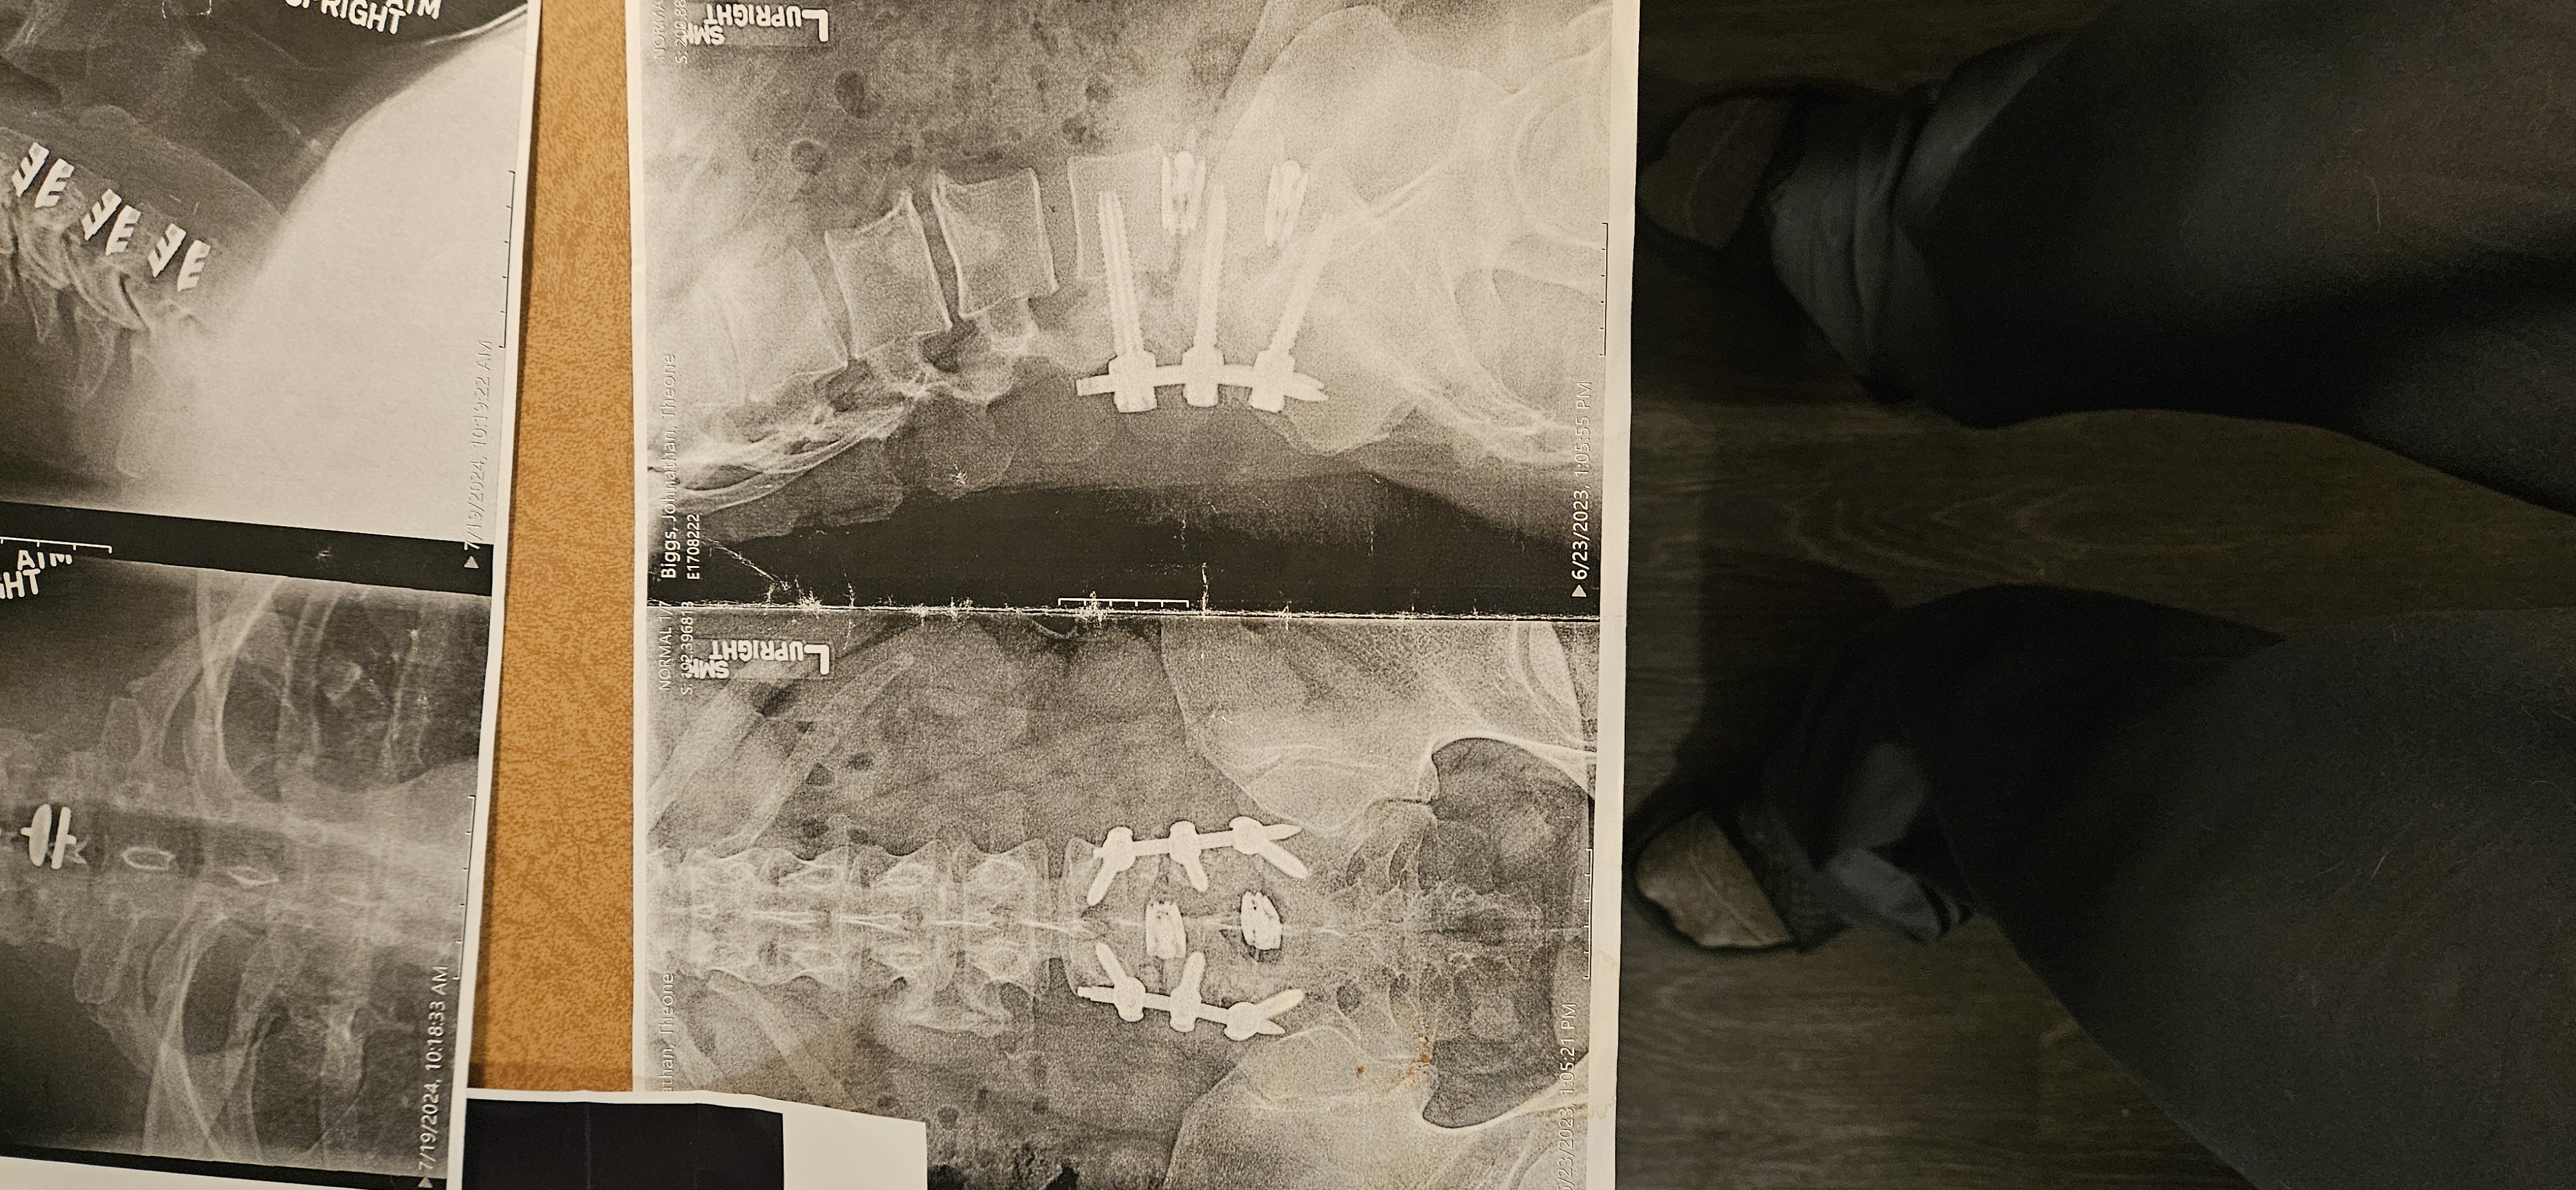

Hello, friends, family, and kind strangers. My name is John Biggs, and I'm reaching out from Fargo, North Dakota, with a heavy heart but hopeful spirit. For years, I've been battling severe back and neck issues that have turned my life upside down. What started as chronic pain from an injury escalated into a series of surgeries—I've undergone multiple procedures on my spine, including fusions and disc replacements, to try and regain some mobility and relief. Each surgery came with its own set of challenges: long recovery times, physical therapy, and mounting bills that I simply couldn't keep up with on my limited disability income.